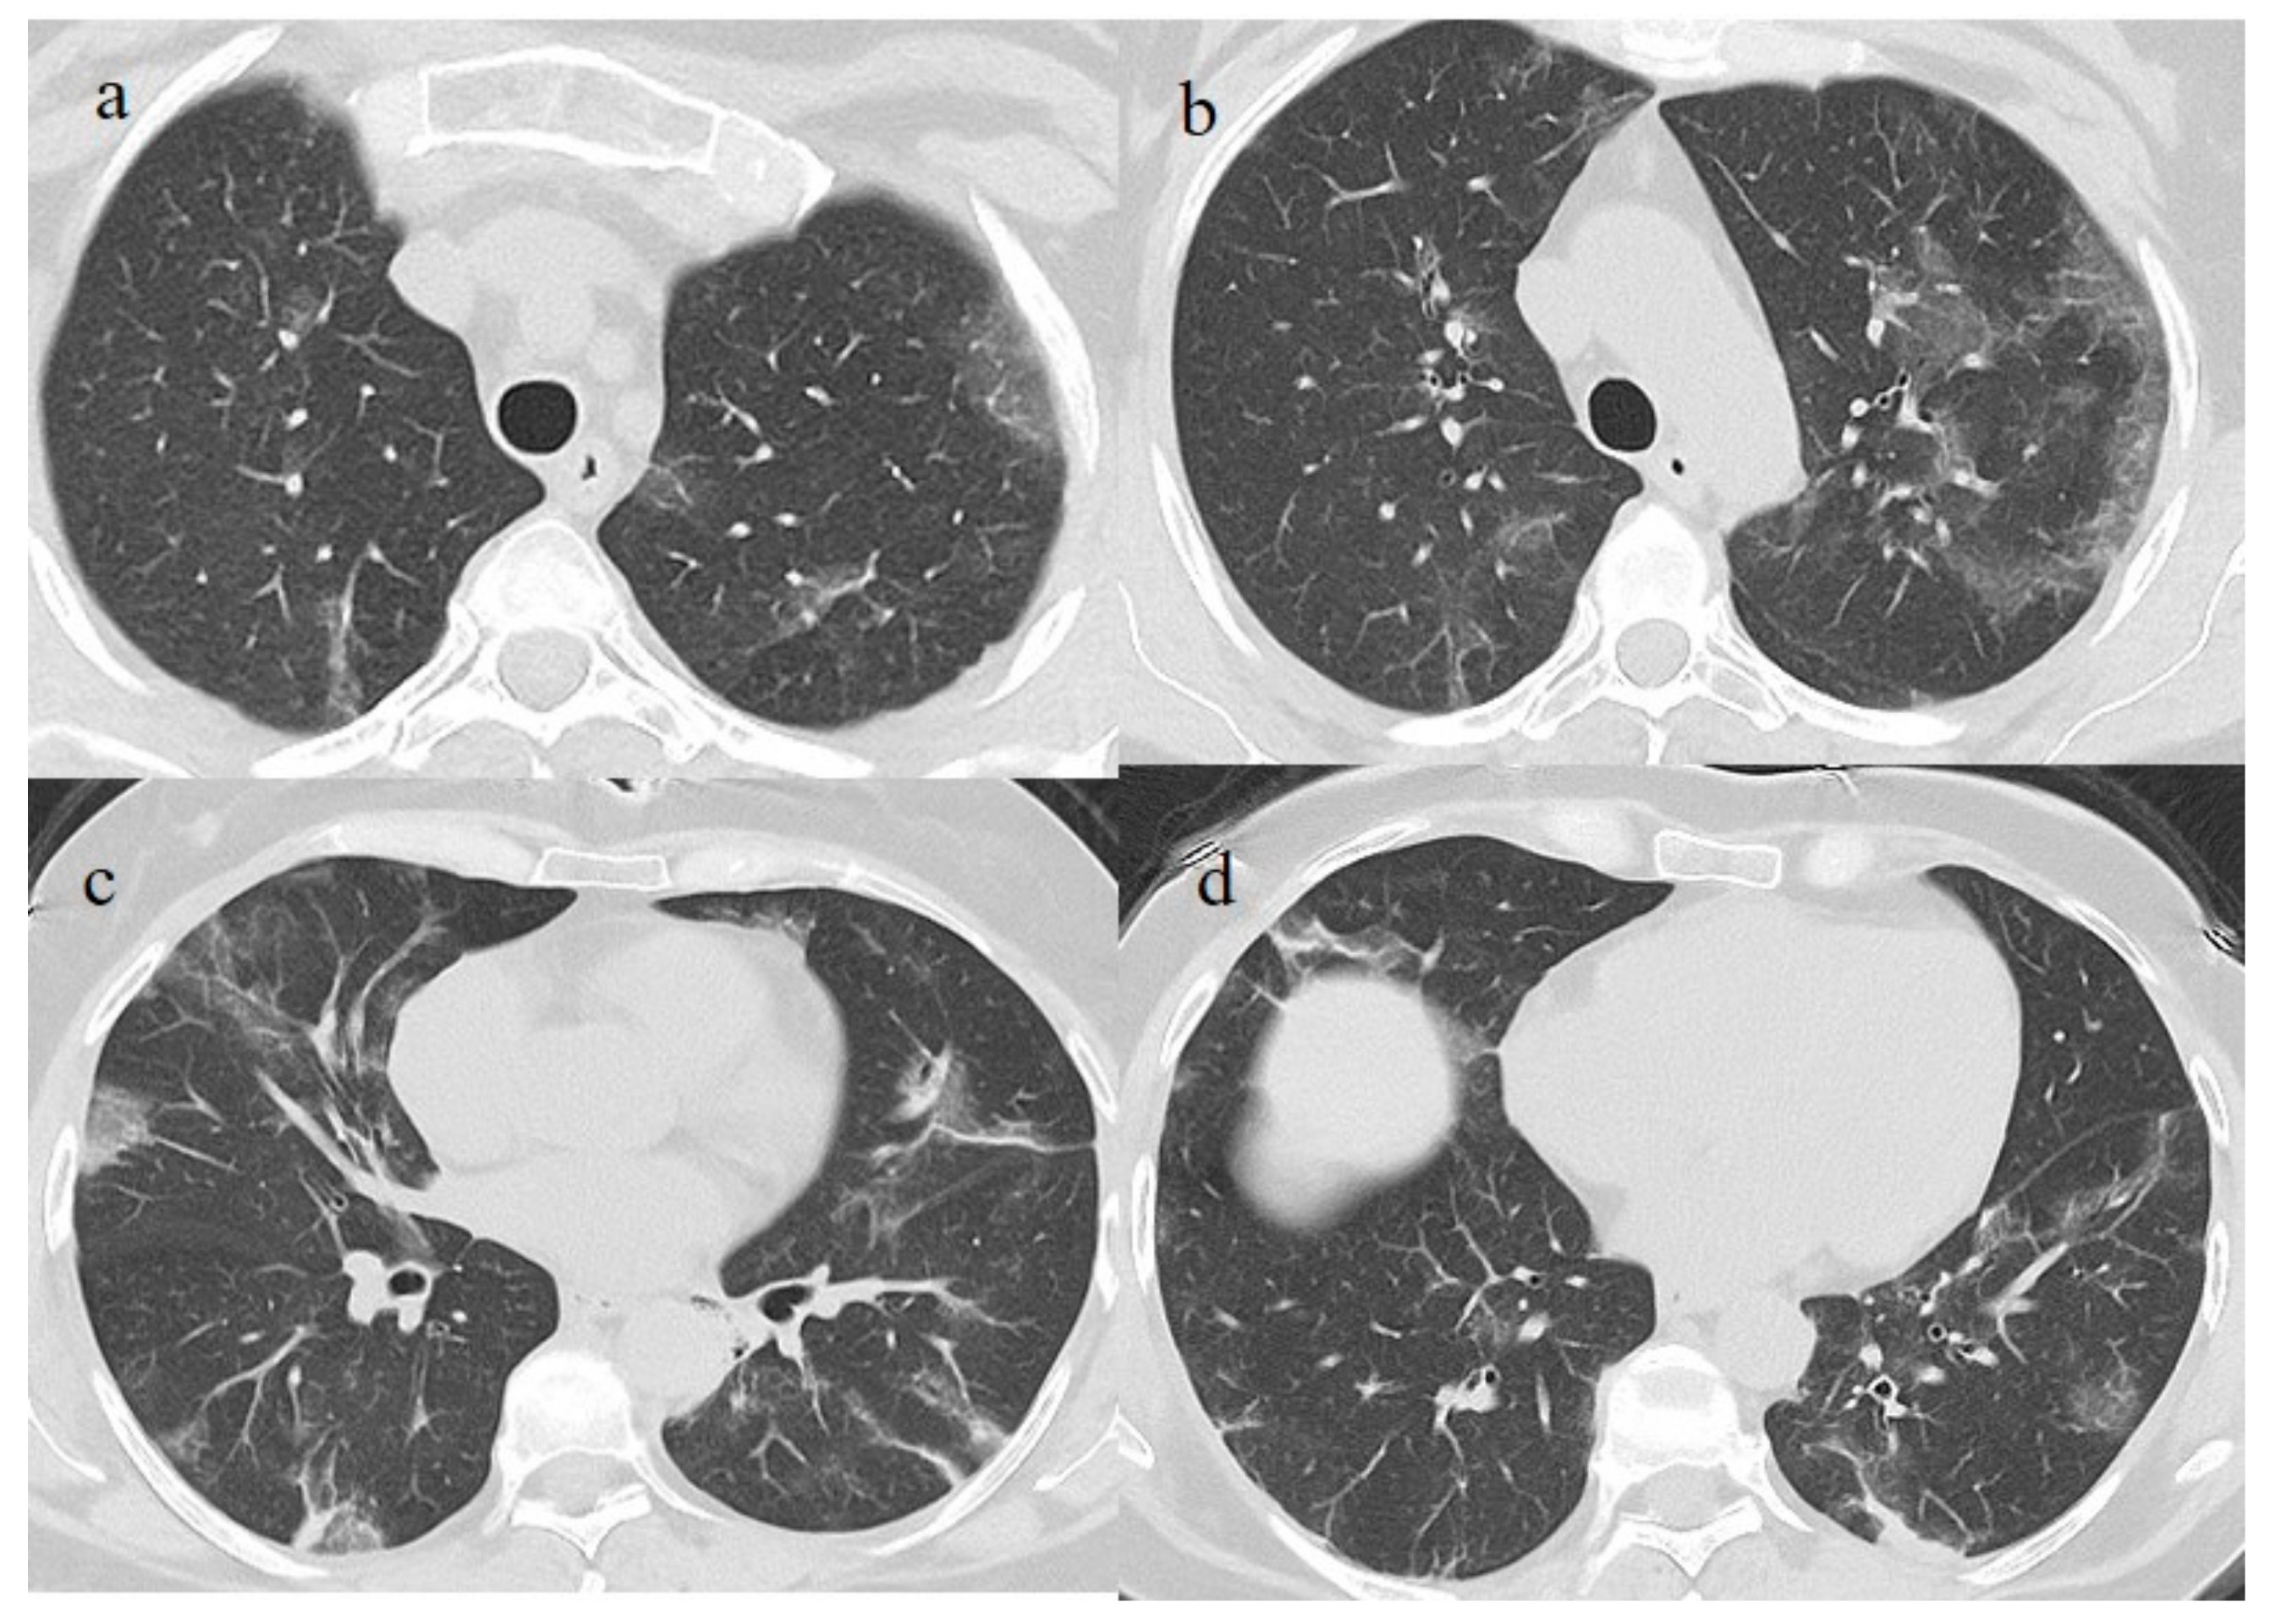

A 51-year-old woman with a history of follicular lymphoma in remission in September 2020, and with a previous SARS-CoV-2 infection in November 2020, received only one dose (according to the current evidence) [22,23] of the Pfizer mRNABNT162b vaccine on 7 April 2021. The patient had been undergoing treatment with rituximab since September 2020. However, the patient never developed an immune response to SARS-CoV-2 as confirmed by serology, and she had shown a persistent mild positivity on RT-PCR for SARS-CoV-2 since the day of vaccination. A few days after the vaccination, her clinical condition worsened, with dyspnea, fever, and a SO2 of 96%. One week after the vaccination, she visited the emergency room of a tertiary hospital and underwent a chest computed tomography (CT). The chest CT showed multilobe areas of ground glass (GGO) in a peripheral and central distribution in the acute phase. The patient’s RT-PCR for SARS-CoV-2 continued to be positive. After 2 months, on 7 June, she visited the emergency room of our hospital for the worsening of dyspnea and fever. On admission, another NP/OP swab tested positive for SARS-CoV-2 without the detection of any variants. Her SO2 was at 90%. A chest CT was performed in the emergency department, showing GGO in a peripheral and central distribution with a CT-SS of 9/20 (Figure 2).

The patient’s NP/OP swabs continued to test positive for SARS-CoV-2 on 11 and 15 June. Another chest CT was repeated on 17 June, which showed an evolution of some GGO areas in consolidative areas with the same CT-SS. However, the chest CT also showed some new GGO areas in the left superior lobe (Figure 3).

On admission, another NP/OP swab tested positive. The chest CT continued to show GGO areas, although the CT-SS remained stable (Figure 4). Treatment with ceftriaxone (1 g once daily with intravenous administration) was started, along with prednisone (25 mg once daily with oral administration for 10 days).

Figure 2. Chest CT performed in the emergency department on 7 June, showing GGO areas with a peripheral and central distribution in a typical presentation of COVID-19 pneumonia in a multifocal involvement. (a,b) GGO areas in the superior lobes, (c) the middle and left superior lobes, and (d) the inferior lobes.

Figure 3. Chest CT performed on 17 June. (a,b) Some new GGO areas in the left superior lobe with the disappearance of the GGO areas in the superior lobe. (c,d) An evolution in crazy paving and the consolidation of some previous GGO in the middle and inferior lobes.

Figure 4. Chest CT performed on 3 July, showing in the image (a) that some GGO areas remained bilaterally present in the superior lobe and in the image (b) in the middle and inferior lobe with a multifocal distribution.